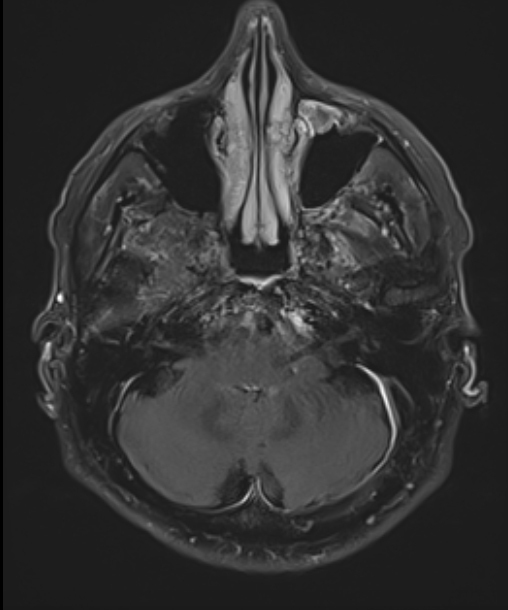

Voici des clichés de sa tomodensitométrie (TDM) cérébrale :

Figure 6 (source : S. Demortière)

Question 9 - Votre (vos) hypothèse(s) diagnostique(s) est (sont) la (les) suivante(s) :

Le fond d’œil montre un œdème papillaire bilatérale = neuropapillite. Ceci doit faire évoquer en premier lieu une HTIC.

L’imagerie vous montre une dilatation des ventricules avec cloisonnement = non communicante : explique alors l’HTIC.